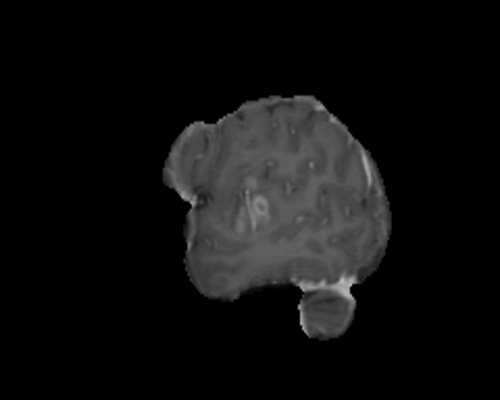

For segmentation, we employ the zero-shot method MedCLIP-SAMv2 [koleilat2024medclip, koleilat2024medclipsamv2]. It works by computing activation maps from a pre-trained CLIP model, and using them as query for the Segment Anything Model (SAM) [kirillov2023segment]. Activation maps are computed using Multi-Modal Information Bottleneck Attribution (M2IB) [wang2023visual], using a target image and a query prompt. Here, we aim at improving the quality of the activation maps on different concepts by leveraging KT. This, in turn, should result in a higher accuracy of the final segmentation. We target four different segmentation tasks: lung nodules segmentation on CT images (UnitoChest), pneumothorax segmentation on CXR images (SIIM Pneumothorax), breast nodule segmentation on ultrasound images (UDIAT), and glioma segmentation in MRIs (BraTS23).

The overall results across all segmentation tasks are presented in Tab. 7. The captions used for inversion are reported in the supplementary material. To compute the M2IB activation maps on the fine-tuned models, we employ descriptive prompts as suggested in [koleilat2024medclipsamv2]. The prompts are reported in Tab. 7 as P1 to P4 for each task. We also report reference results of MedCLIP-SAMv2 on each task. Compared to the original setting of MedCLIP-SAMv2, lung nodules and lung pneumothorax are completely novel concepts. There is also a slight difference in the brain glioma class compared to the original brain tumor task, explained in the supplementary file. We employ three metrics to assess the segmentation quality, namely the Dice-Sørensen Coefficient (DSC), Normalized Surface Distance (NSD), and Intersection over Union (IoU). We report results with different values of fine-tuning learning rate. We can observe an increase in segmentation metrics across all tasks, notably in breast ultrasound (NSD 59.44% to 61.56%) and brain MRIs (NSD 20.97% to 22.26%). For lung nodules and pneumothorax, the improvement is less pronounced, probably because the novelty of the task makes improving more difficult in the MedCLIP-SAM setting. We report some visual examples on breast tumor segmentation in Fig. 5, showcasing the improvements of KT.

Results of knowledge transfer on MedCLIP-SAMv2 with different values of learning rate are shown in Tab. 14. We report illustrative examples of the improvements achieved by knowledge transfer in Fig. 11 and Fig. 12. The captions used for inversion for segmentation can be found in Tab. LABEL:tab:captions-segmentation.

Differences in downstream tasks

As said in the main text, lung nodules and pneumothorax segmentations are novel tasks on which MedCLIP-SAMv2 was not pre-trained. Regarding brain tumors, we employ the BraTS 2023 glioma dataset, which contains brain gliomas in adult patients. With respect to the original performance reported in [koleilat2024medclipsamv2] on brain tumors, we notice a significant gap. However, the preprocessing of the images is quite different, as data from BraTS 2023 is more heavily preprocessed (e.g. skull stripping) than in [koleilat2024medclipsamv2]. We were not able to compare MedCLIP-SAMv2 on the original data, as, at the time of writing, details about the data split are missing.